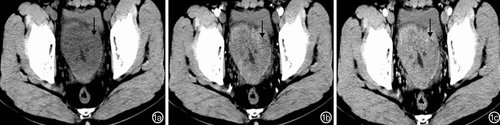

小肠淋巴瘤患者CT检查结果主要表现为局限性或节段性中重度肠壁不均匀性增厚,病变肠壁明显不均匀强化(图1);肠外主要表现为淋巴结、肝、脾肿大。

图1回肠淋巴瘤患者CT检查特征:回肠壁重度不均匀性增厚(↓)、局部肠腔狭窄 1a:平扫肠壁不均匀,低密度;1b:动脉期肠壁明显不均匀强化;1c:静脉期肠壁不均匀强化程度较动脉期增加